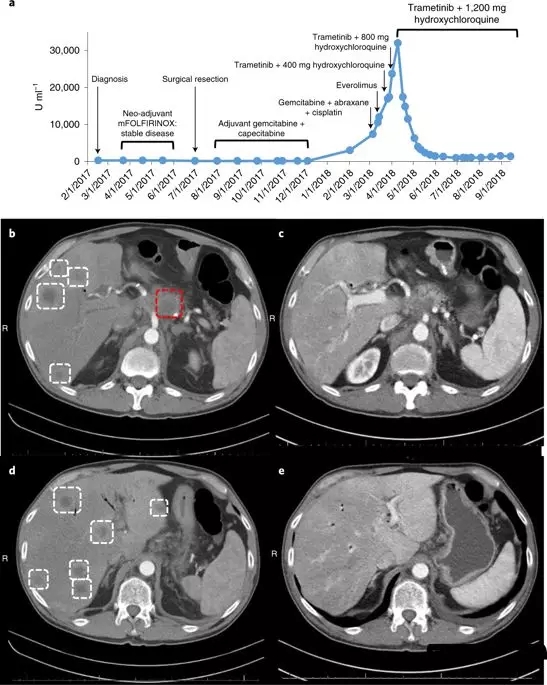

这种联合疗法的效果在一位晚期胰腺癌患者身上同样得到了证实,这位患者在手术后,接受了几次化疗,但不幸的是癌症复发并转移了,目前已经没有很好的治疗方案,

Hydroxychloroquine(羟氯喹)和trametinib(曲美替尼)分别被美国食品和药物管理局批准用于治疗疟疾和黑色素瘤。

这名患者接受了 trametinib和hydroxychloroquine治疗,令患者和医生震惊的是,奇迹出现了,2个月内,患者的胰腺癌标志物CA 19-9的血液水平下降了95%。4个月后,他体内的癌症数量减少了50%。对于胰腺癌来说,这是一个非常了不起的反应!

用曲美替尼加羟氯喹(T / HCQ)治疗胰腺癌患者导致肿瘤标志物癌抗原19-9(CA19-9)和总体肿瘤负荷减少。